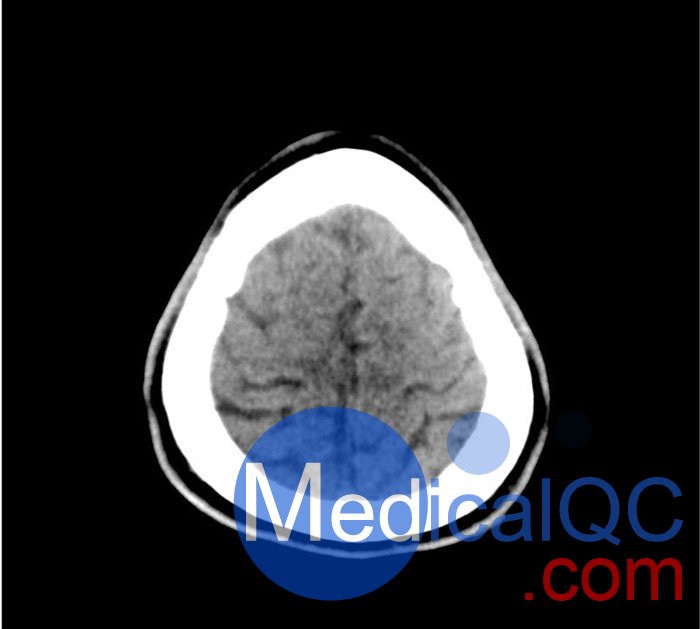

50-01頭部CT模體,50-01腦中風(fēng)頭部模體,50-01腦出血頭部模體模擬了具有中風(fēng)和出血模式的頭部。它覆蓋枕骨大孔的頂點(diǎn)。

該模型可用于 CT(包括 CBCT)以評(píng)估和優(yōu)化成像性能和 AI 支持的診斷。它也適用于培訓(xùn)目的。

該模型提供了對(duì)常見大腦病理、軟組織和骨組織的詳細(xì)而逼真的模擬??諝饪障短畛溆屑s-160HU的纖維素-聚合物復(fù)合材料。

50-01頭部CT模體,50-01腦中風(fēng)頭部模體,50-01腦出血頭部模體影像效果圖: